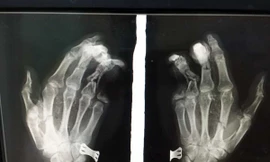

TPO - Vừa cắm dây sạc điện thoại vừa chơi game khiến điện thoại phát nổ, nam thanh niên phải vào bệnh viện cấp cứu trong tình trạng bàn tay trái bị dập nát, ngón út bị cụt mất 2 đốt.